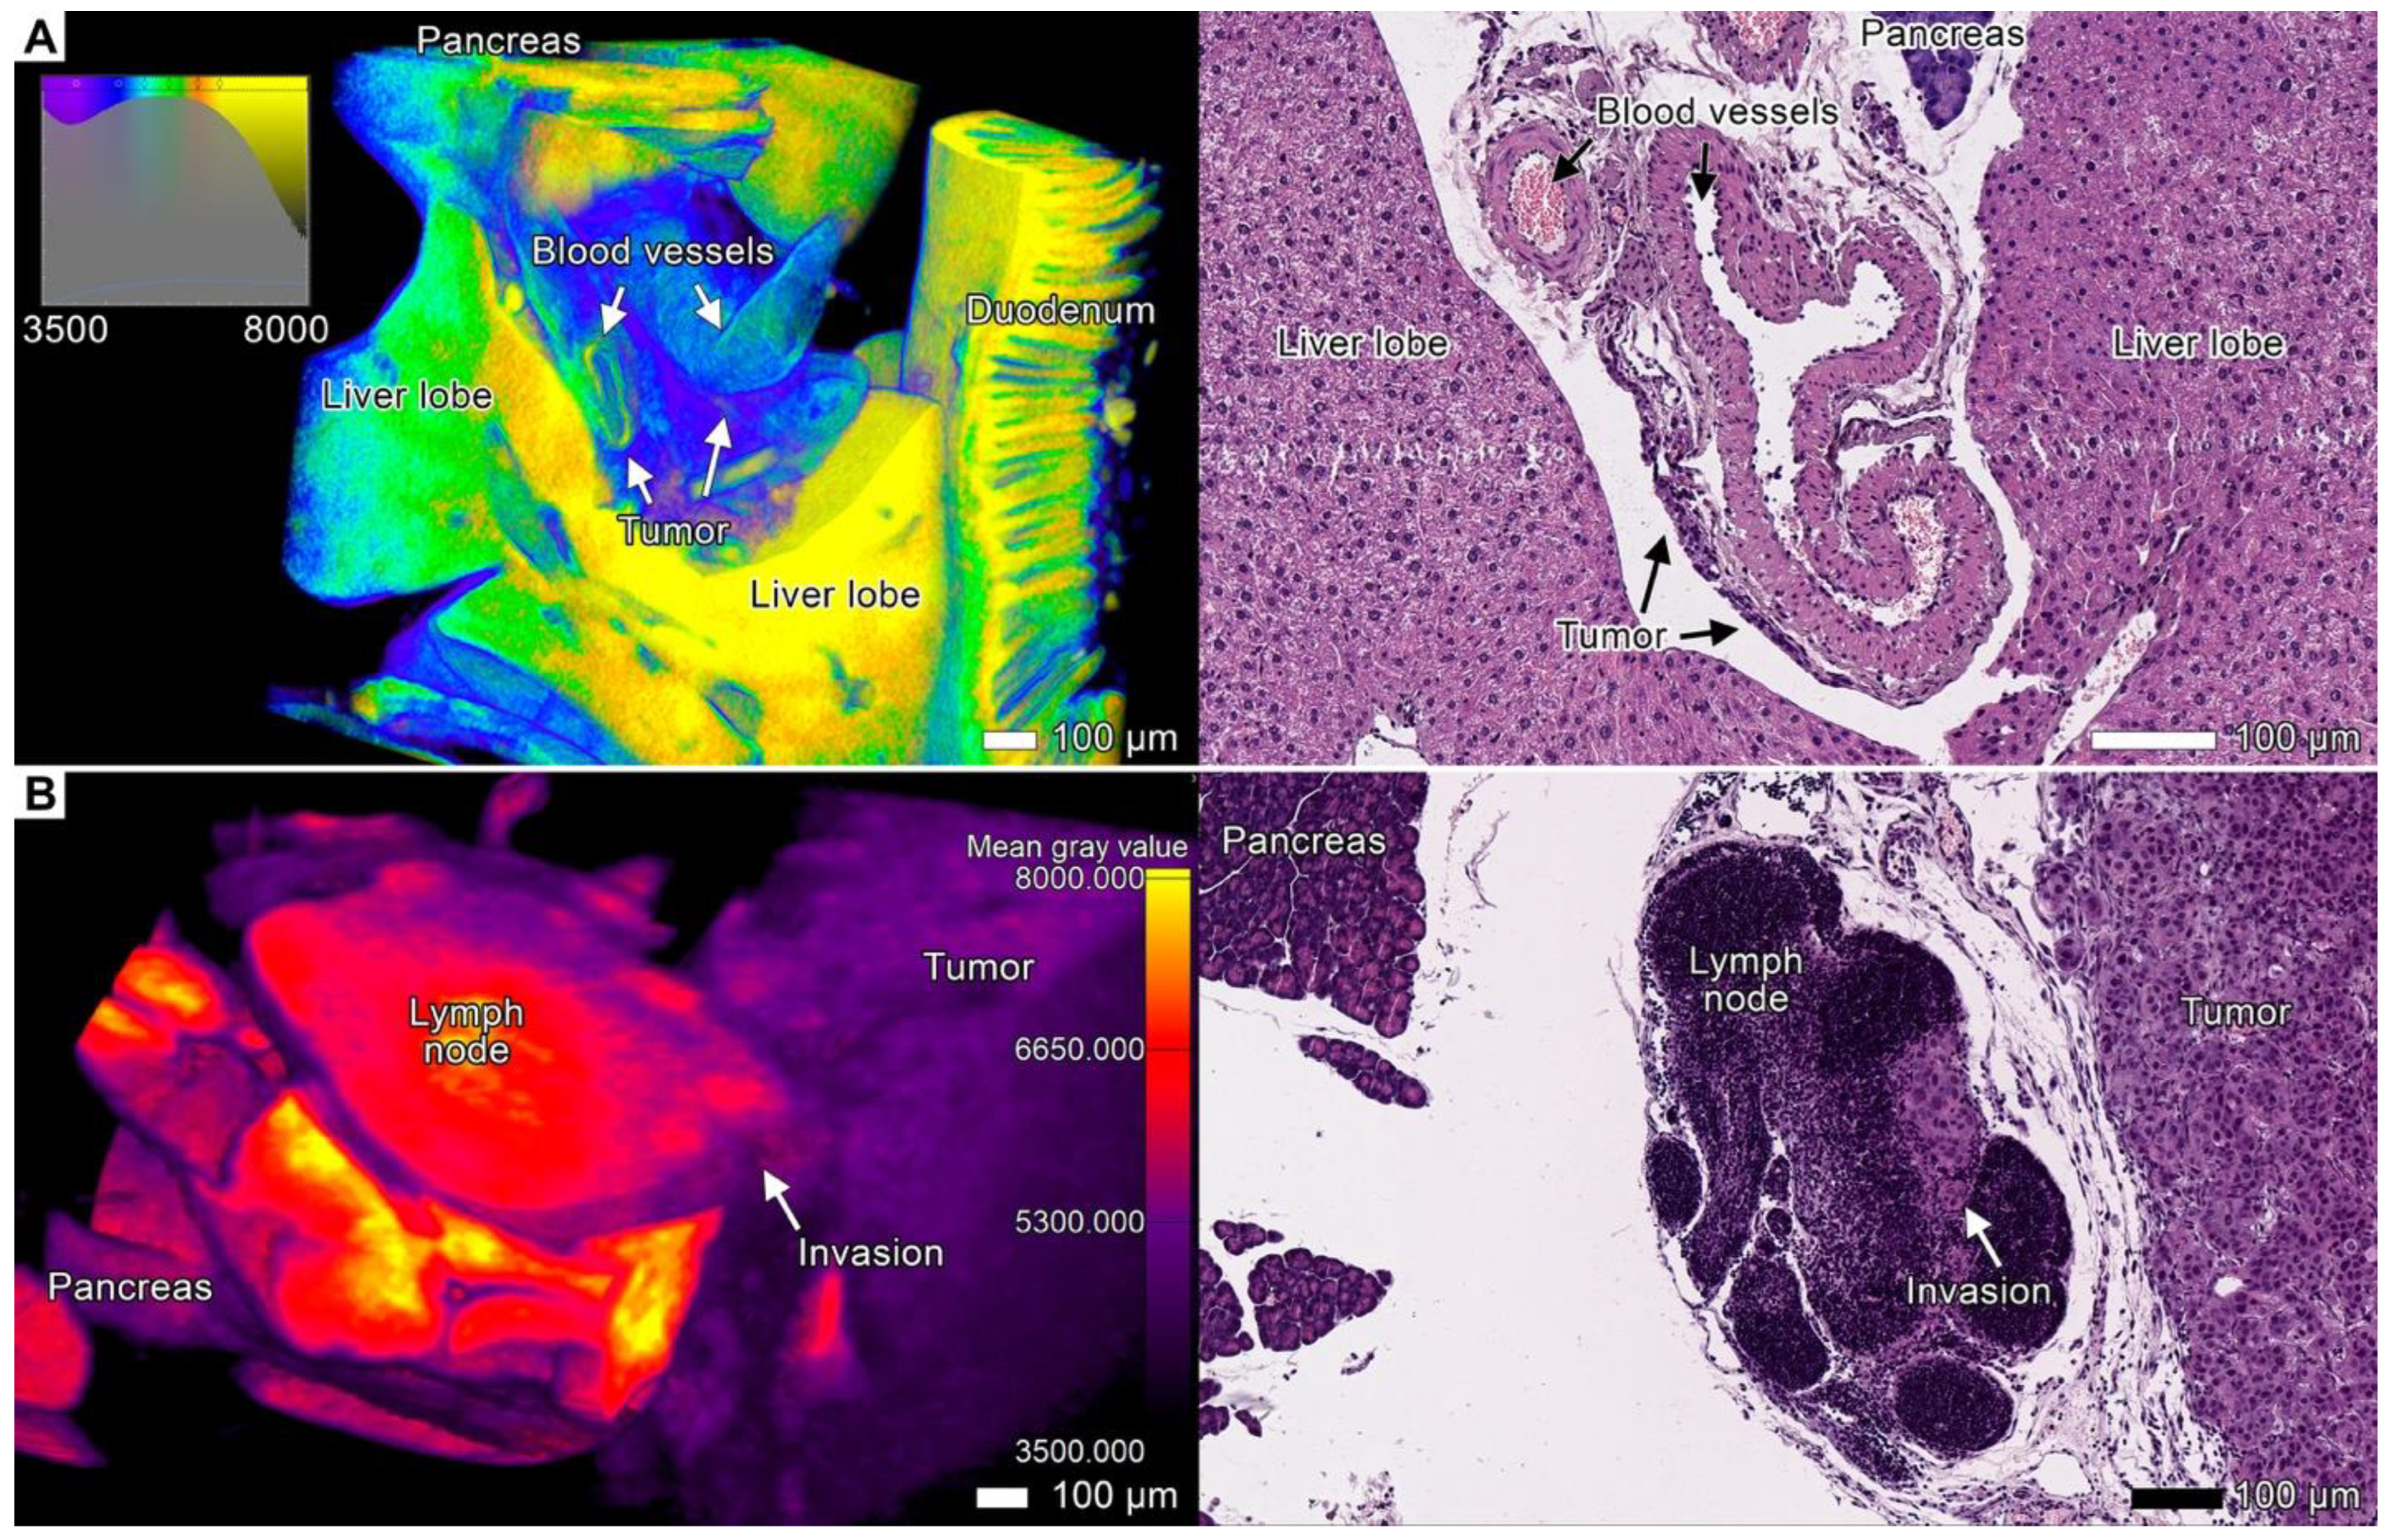

3.4. Tumor Invasion into the Pancreas

3.8. Expanding the Concept of Tumor Clusters

4.4. Tumor Budding Revisited